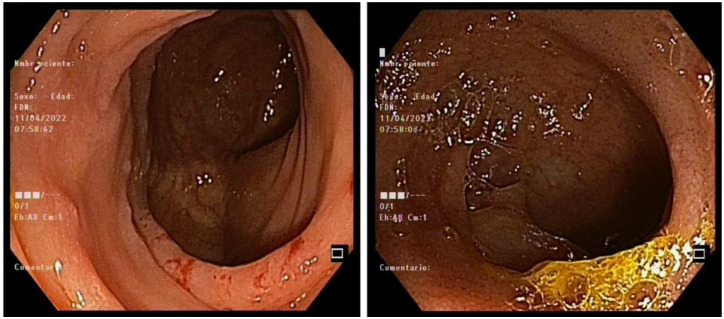

Dasatinib is a second-generation tyrosine kinase inhibitor employed for chronic myeloid leukemia (CML) treatment that achieves high rates of prolonged and complete molecular responses (MR). Among the adverse effects reported, it has been associated with hemorrhagic complications, mainly due to its inhibiting effects on platelet functions. In addition, immune alterations induced by dasatinib may elevate the risk of bleeding and cytomegalovirus (CMV) infection, particularly in the gastrointestinal tract, thus contributing to the development of hemorrhagic colitis. In this case report, we highlight three cases of CML receiving treatment with dasatinib where CMV hemorrhagic colitis occurred. All of them exhibited iron deficiency anemia as a premature clinical manifestation in the absence of intestinal symptoms, unlike cases previously reported in the literature. CMV infection was confirmed with stool samples or tissue quantitative polymerase chain reaction and/or immunohistochemistry staining in colon biopsies. All three cases could be managed with valganciclovir and iron supplements in an outpatient setting. Management strategies of dasatinib during and after CMV infection varied, as they are not yet established and need to be individualized based on the gravity of symptoms and disease state. Iron deficiency anemia during dasatinib treatment should raise suspicion for the potential presence of CMV colitis, prompting endoscopic studies to rule out this complication, even if intestinal symptoms are not present.